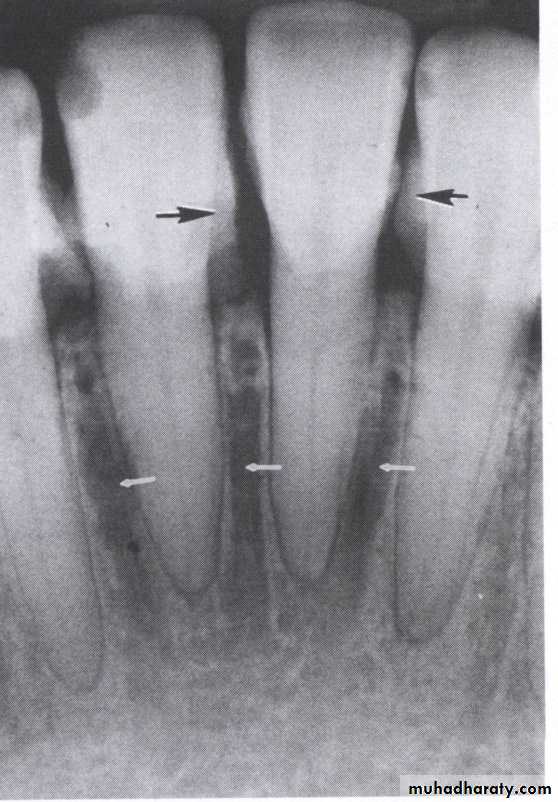

The normal alveolar crest lies 1 to 1.5 mm below the adjacent CEJs and forms a sharp angle with the lamina dura of the

adjacent tooth.

Between the anterior teeth the alveolar crest normally is pointed and well corticated.

1. Horizontal bone loss:- When loss occurs on a plane that is parallel with a line drown.

2.Vertical bone loss:- when there is greater bone loss in one tooth than on the adjacent tooth, so the bone level is not parallel with a line joining the CEJ.